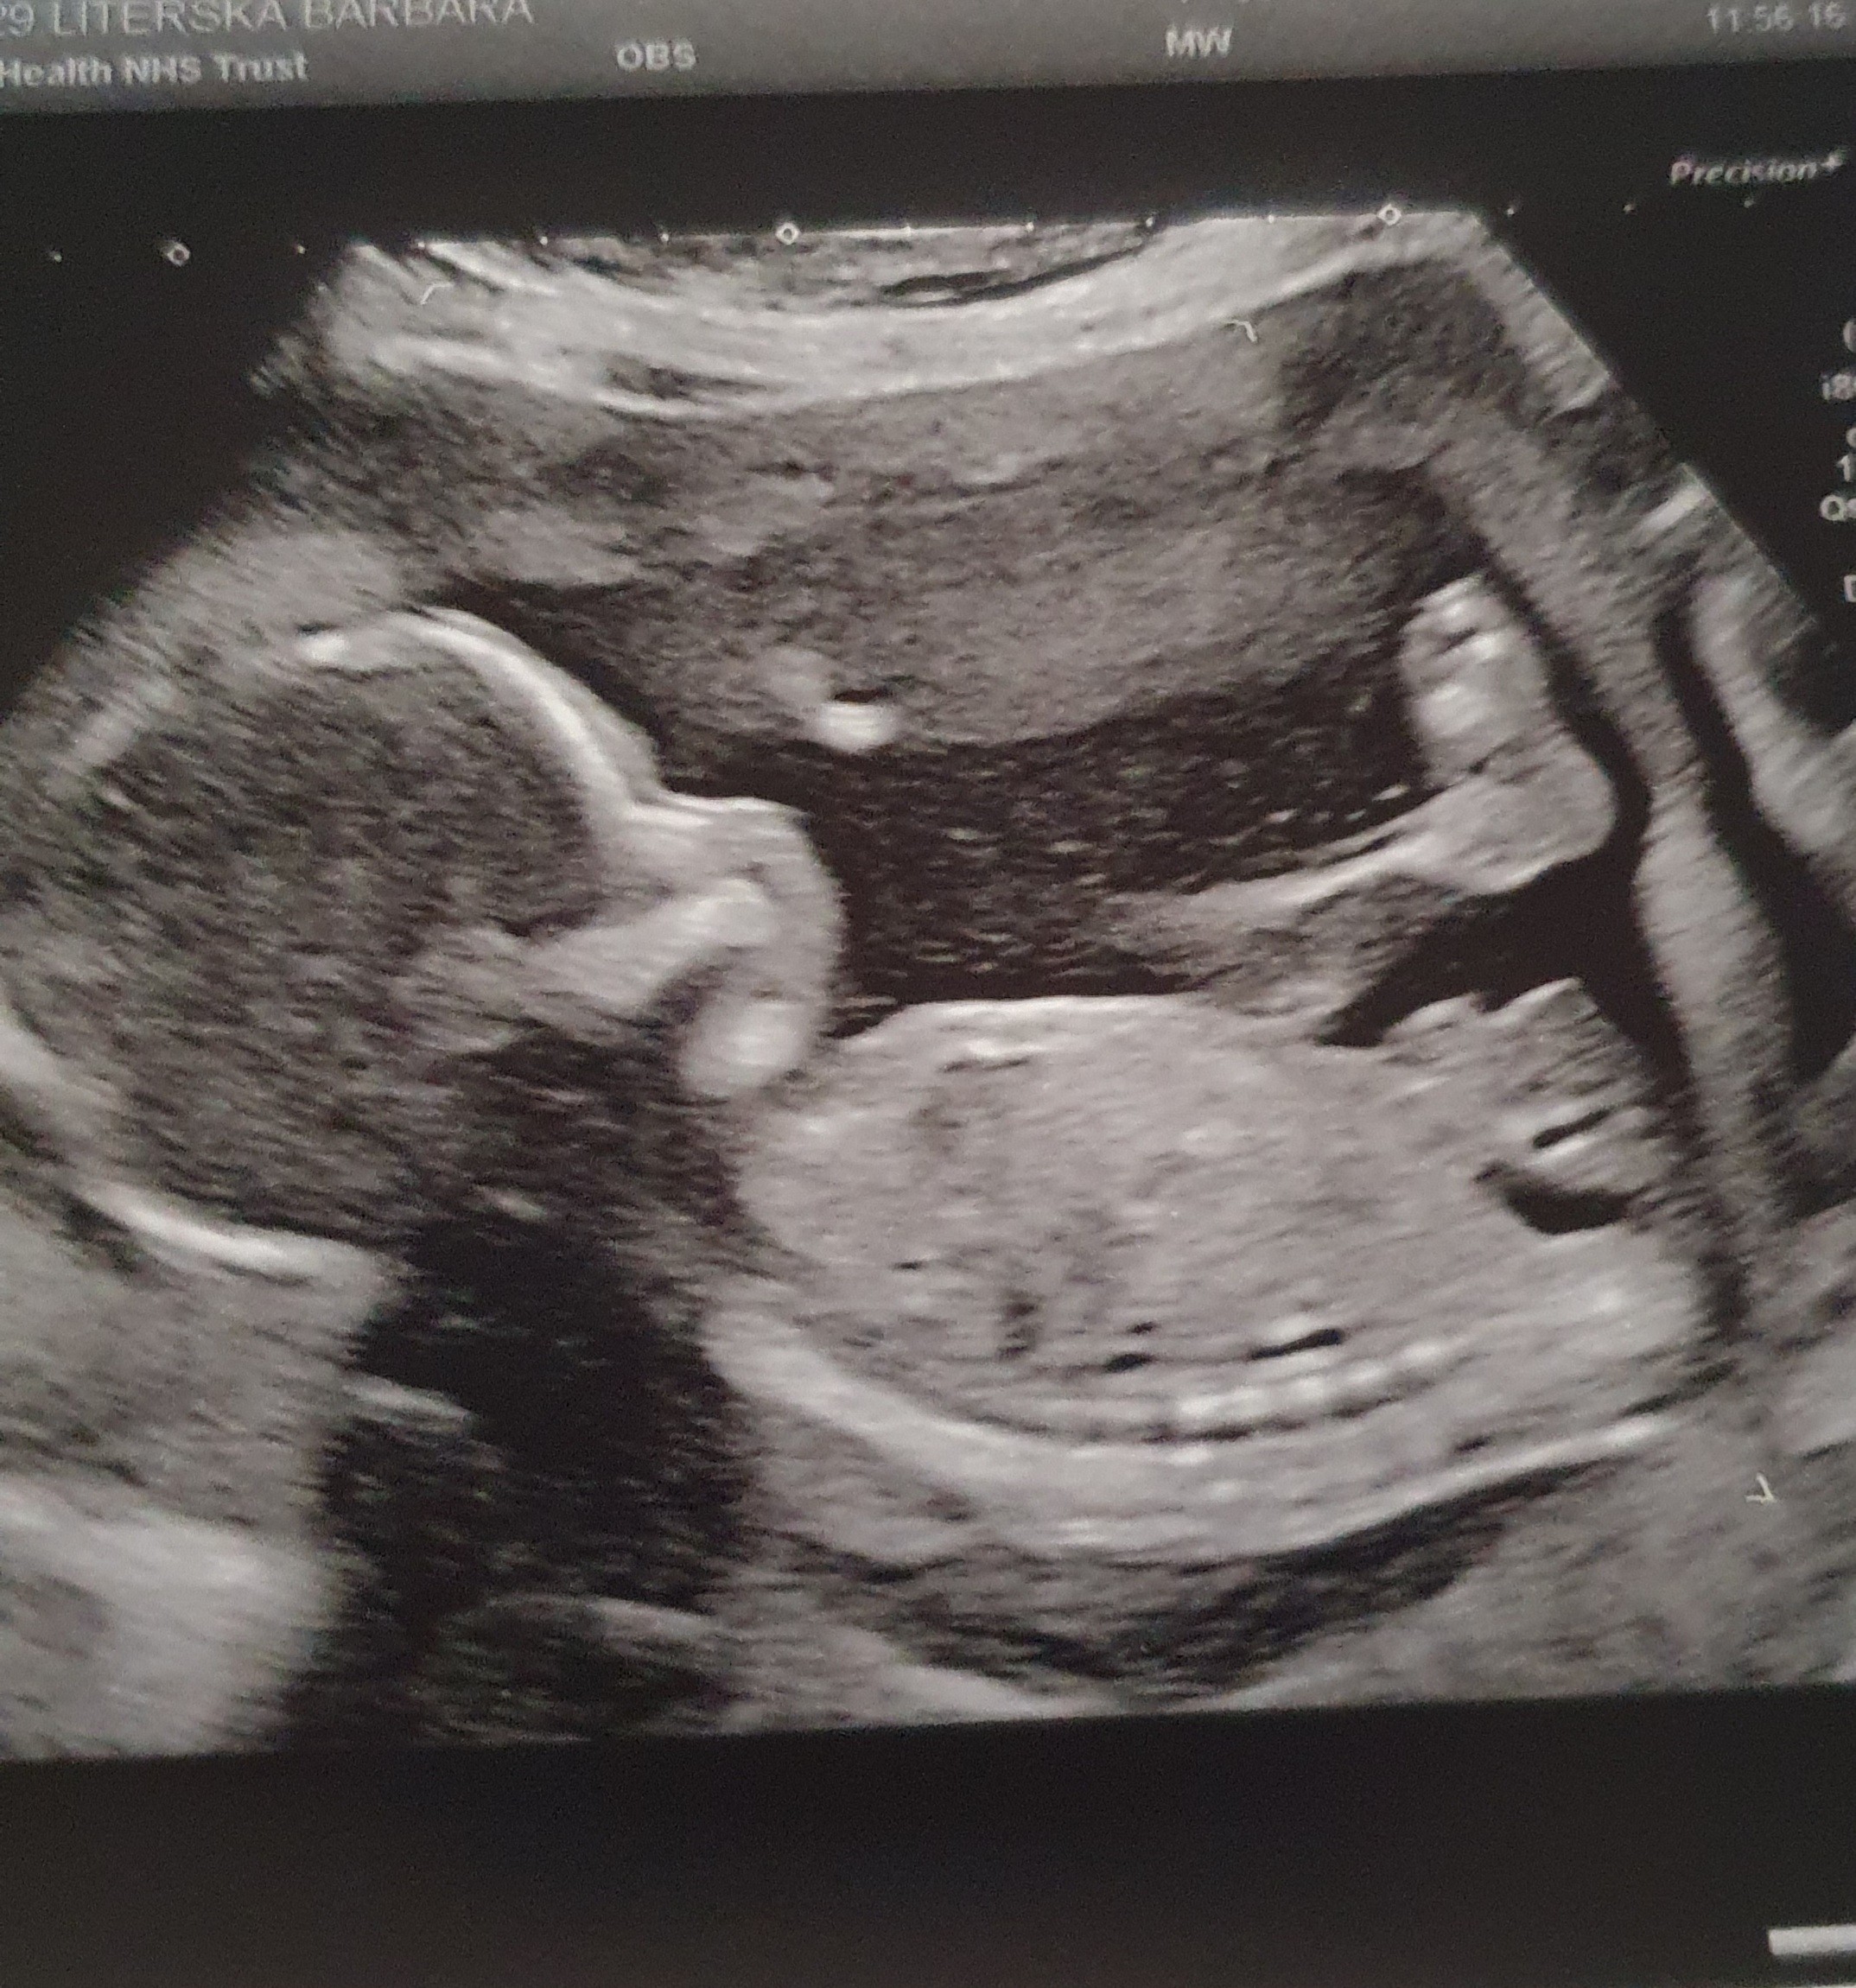

Wogole dali mi jedno zdjęcie z USG a tam wielka stopa na pierwszym planie 😆

Piękne te widoki !!!